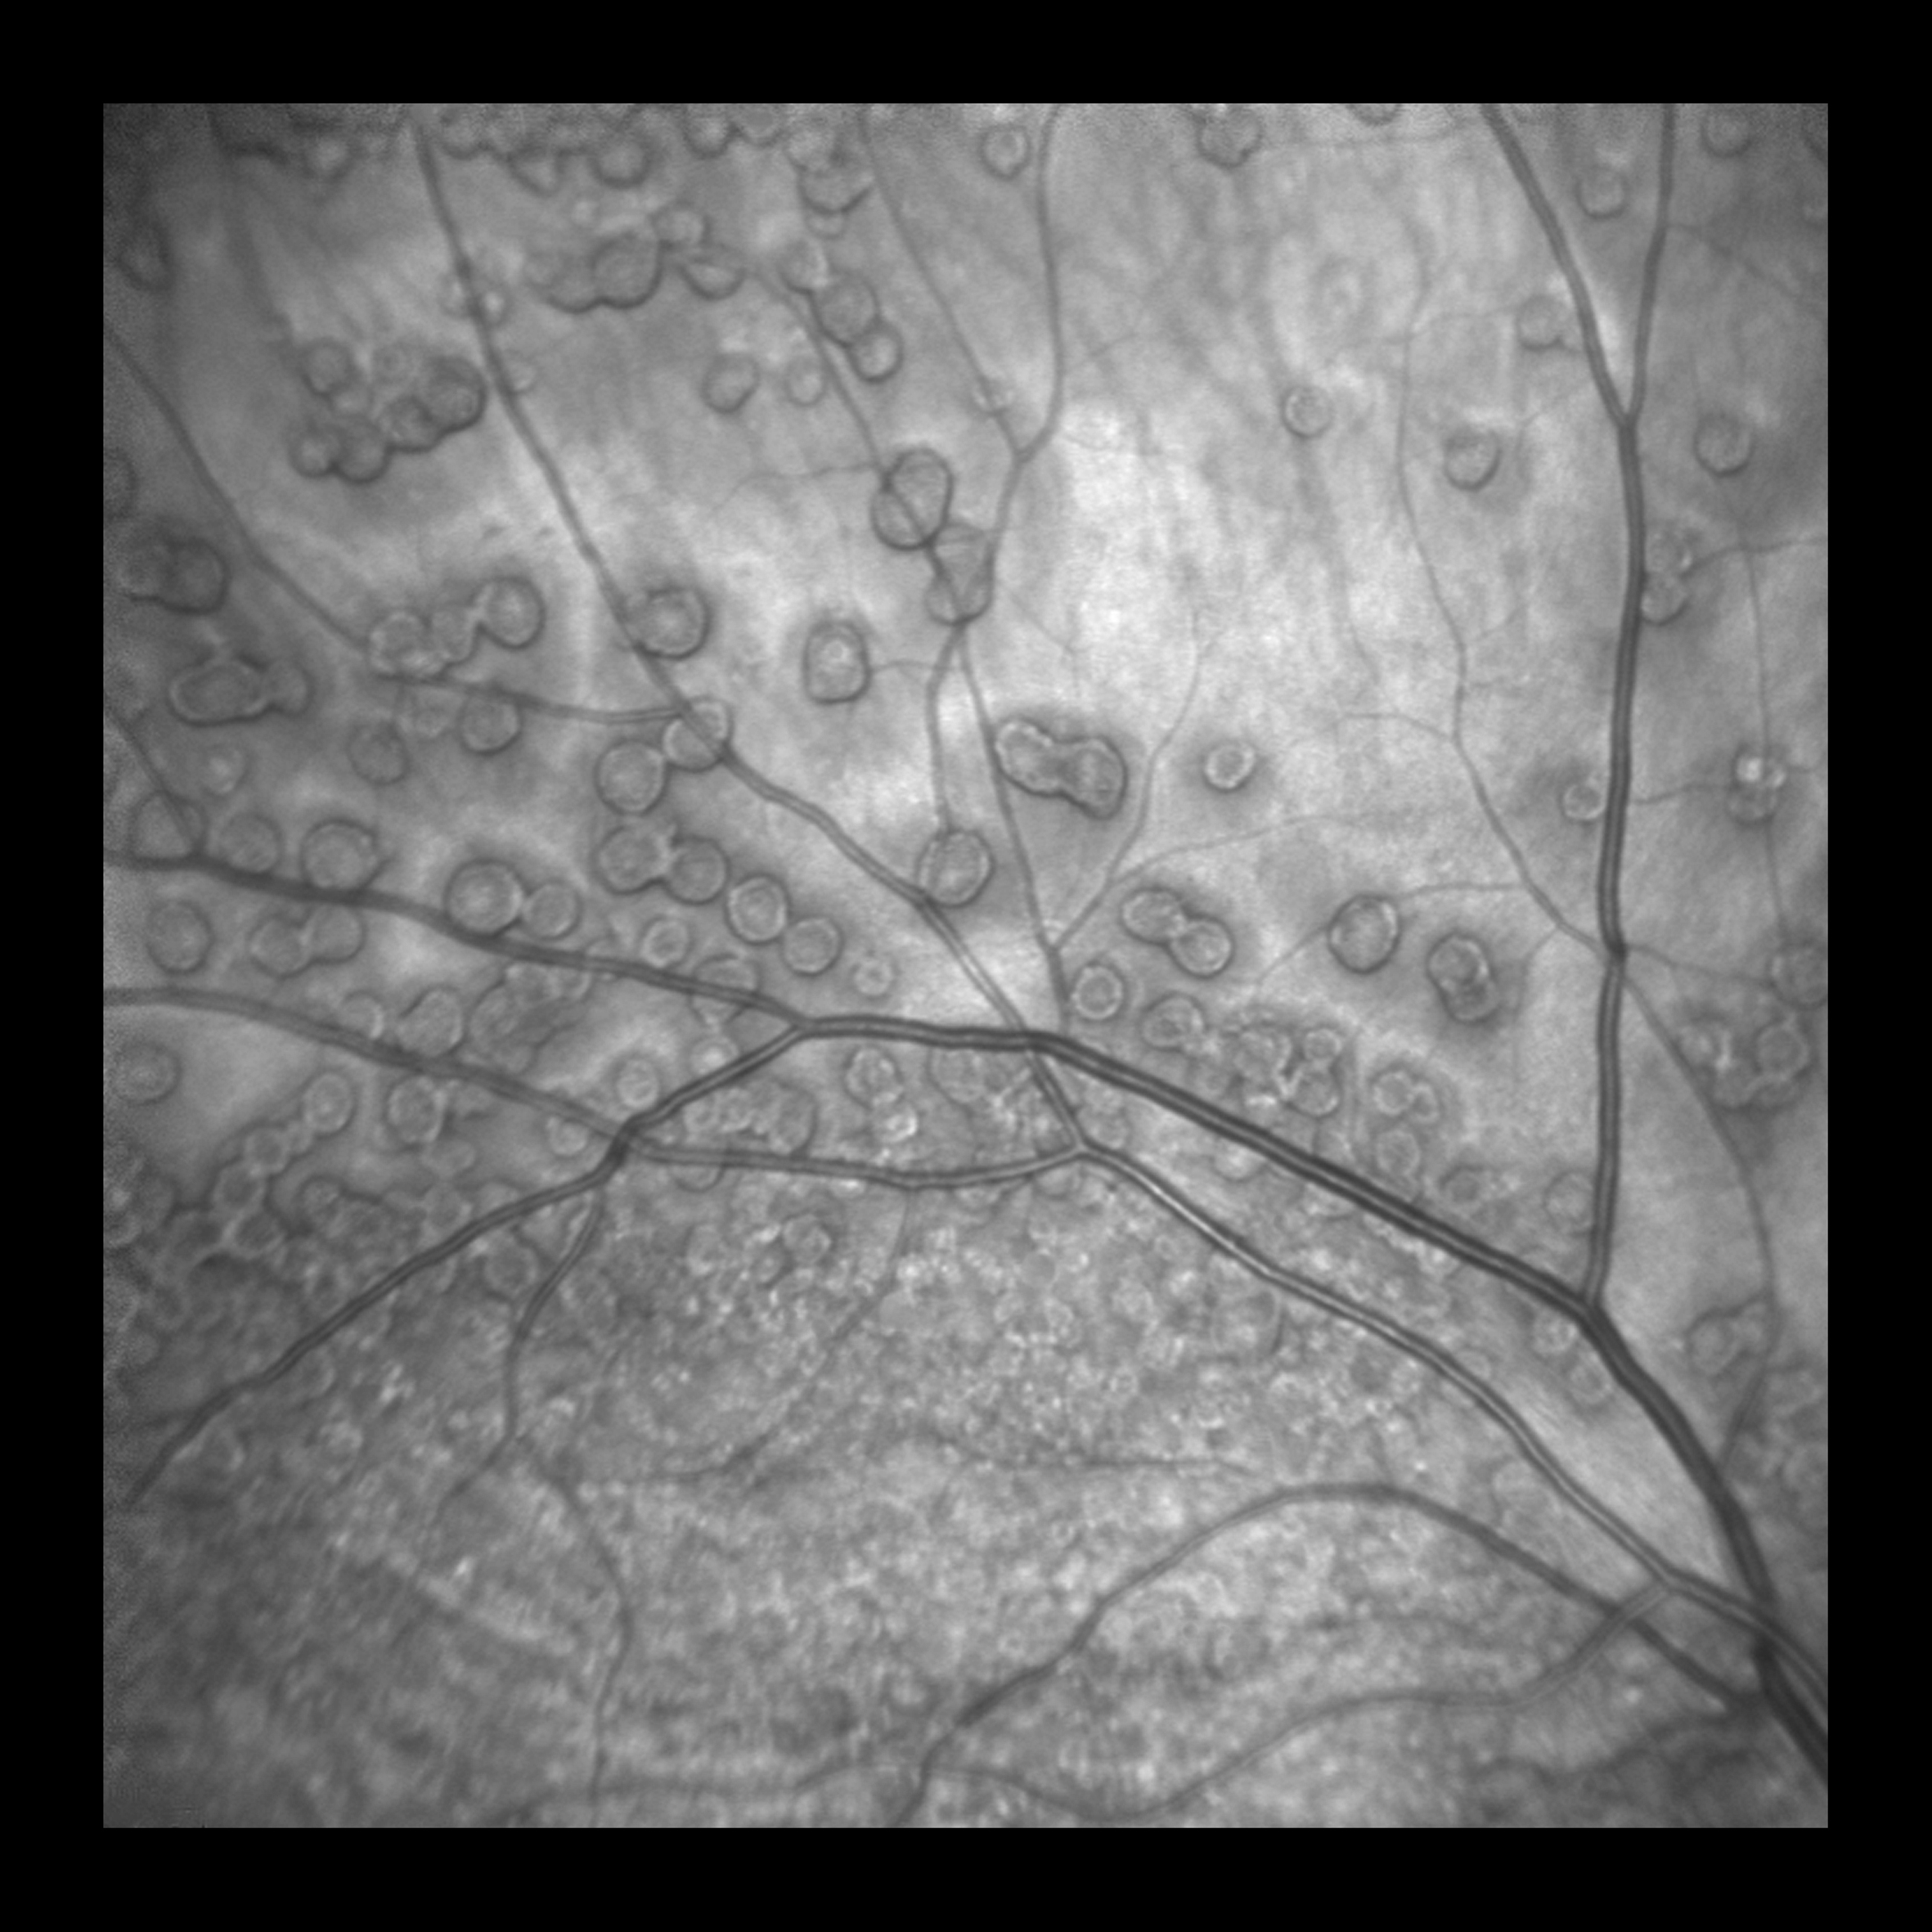

Retinal Drusen Presented by Barbara Klemenc This photograph received Honorable Mention, Monochromatic in the 2025 OPS Scientific Exhibit. Filed Under Retina OPS Photo